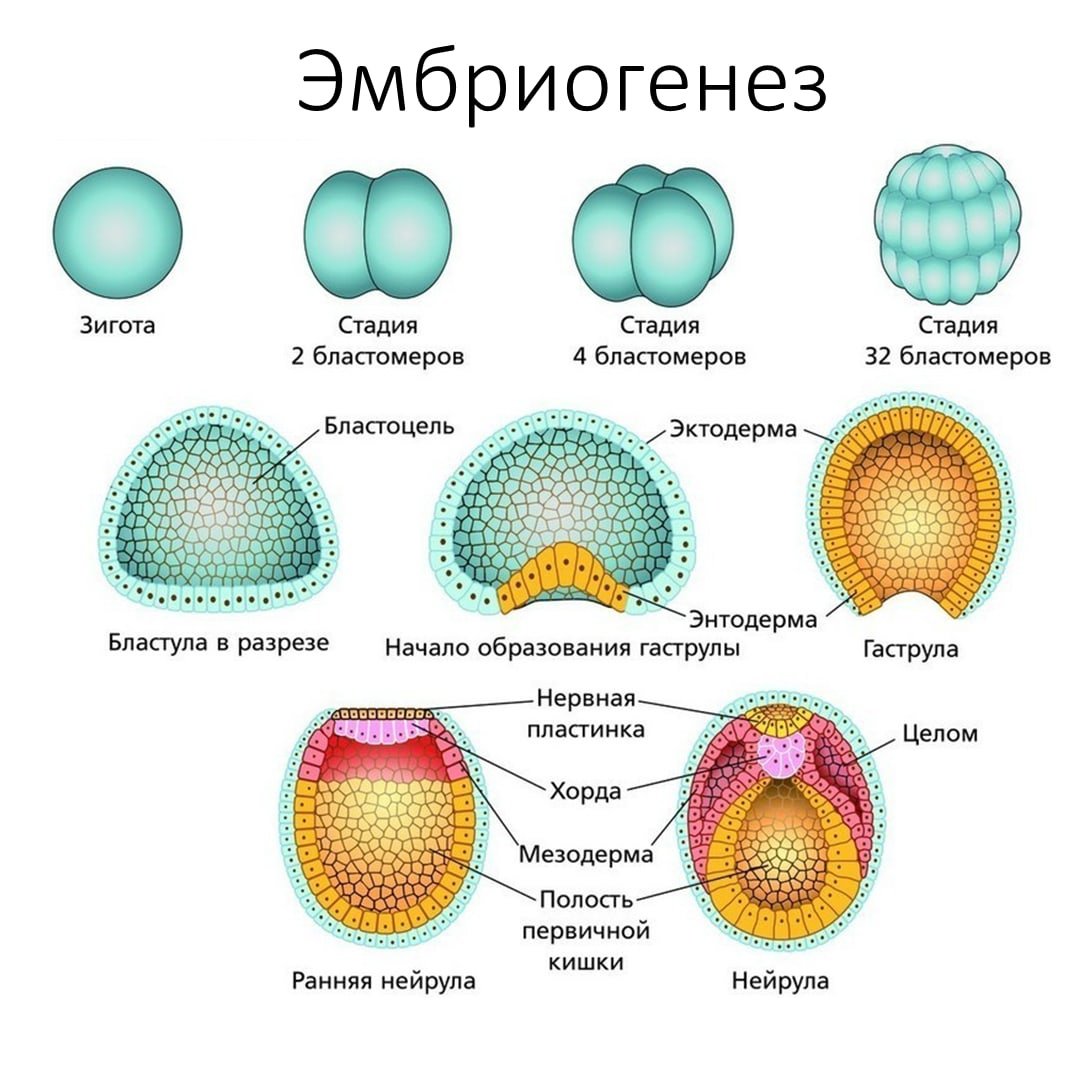

Раздел: Визуальные уроки